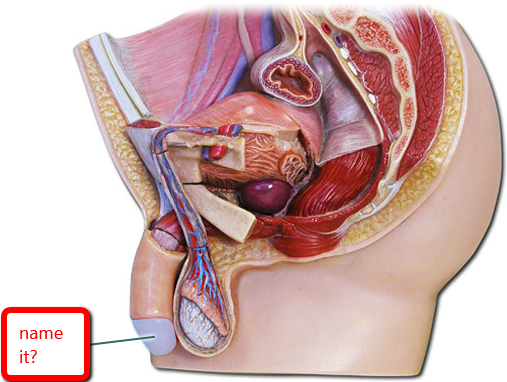

Anus

Bulbourethral gland (male)

Bulbourethral gland (female)

Clitoris

Corpora cavernosa (pl.) Corpus Cavernosum (s.)

Corpus Spongiosum

Epididymis

External urethral orifice (male)

External urethral orifice (female)

Glans penis

Labia majora/minora

Prepuce (=clitoral hood)

Prepuce (=foreskin)

Prostate gland

Prostatic/spongy urethra (males)

Scrotum

Testis (s.) Testes (pl.)

Ureter

Urethra

Urinary Bladder (male)

Urinary Bladder (female)

Vagina

Vaginal orifice

Vas deferens (=ductus deferens)